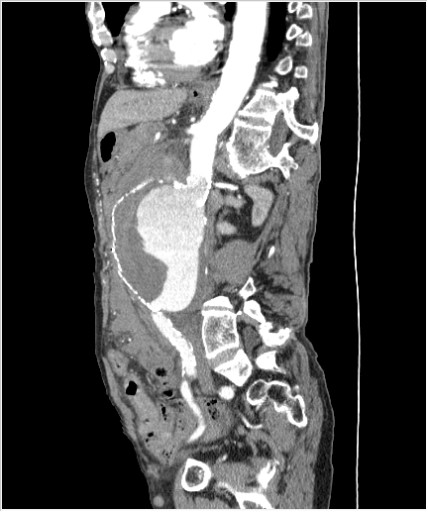

Пациент Т. 64 года, обратился на КТ брюшной полости амбулаторно (!), по направлению семейного врача с диагнозом abdominal mass, буквально: образование брюшной полости.

Huge abdominal aorta aneurism. Simple renal cortical cysts (Bosniak type 1).